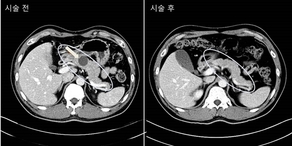

췌장암 위험 높은 물혹, 수술 없이 내시경으로 제거